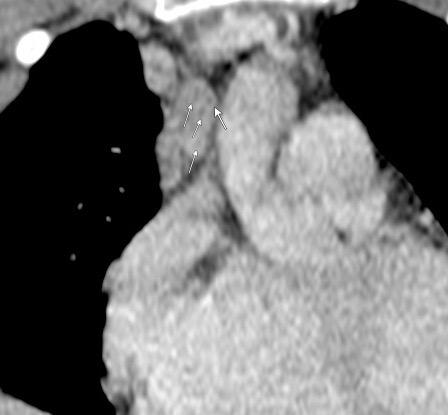

136. PERLAS NEGRAS, SIGNO DE LAS

Ramana. RV et al. The “Cluster of black pearls” sign of sarcoid lymphadenopathy: a new sign on thin-section contrast-enhanced multidetector CT. Clinical Radiology 2017